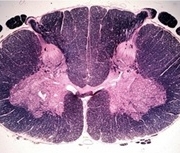

Tracts and Nuclei

Please click one of the following photos to enter the respective section.

Section #4